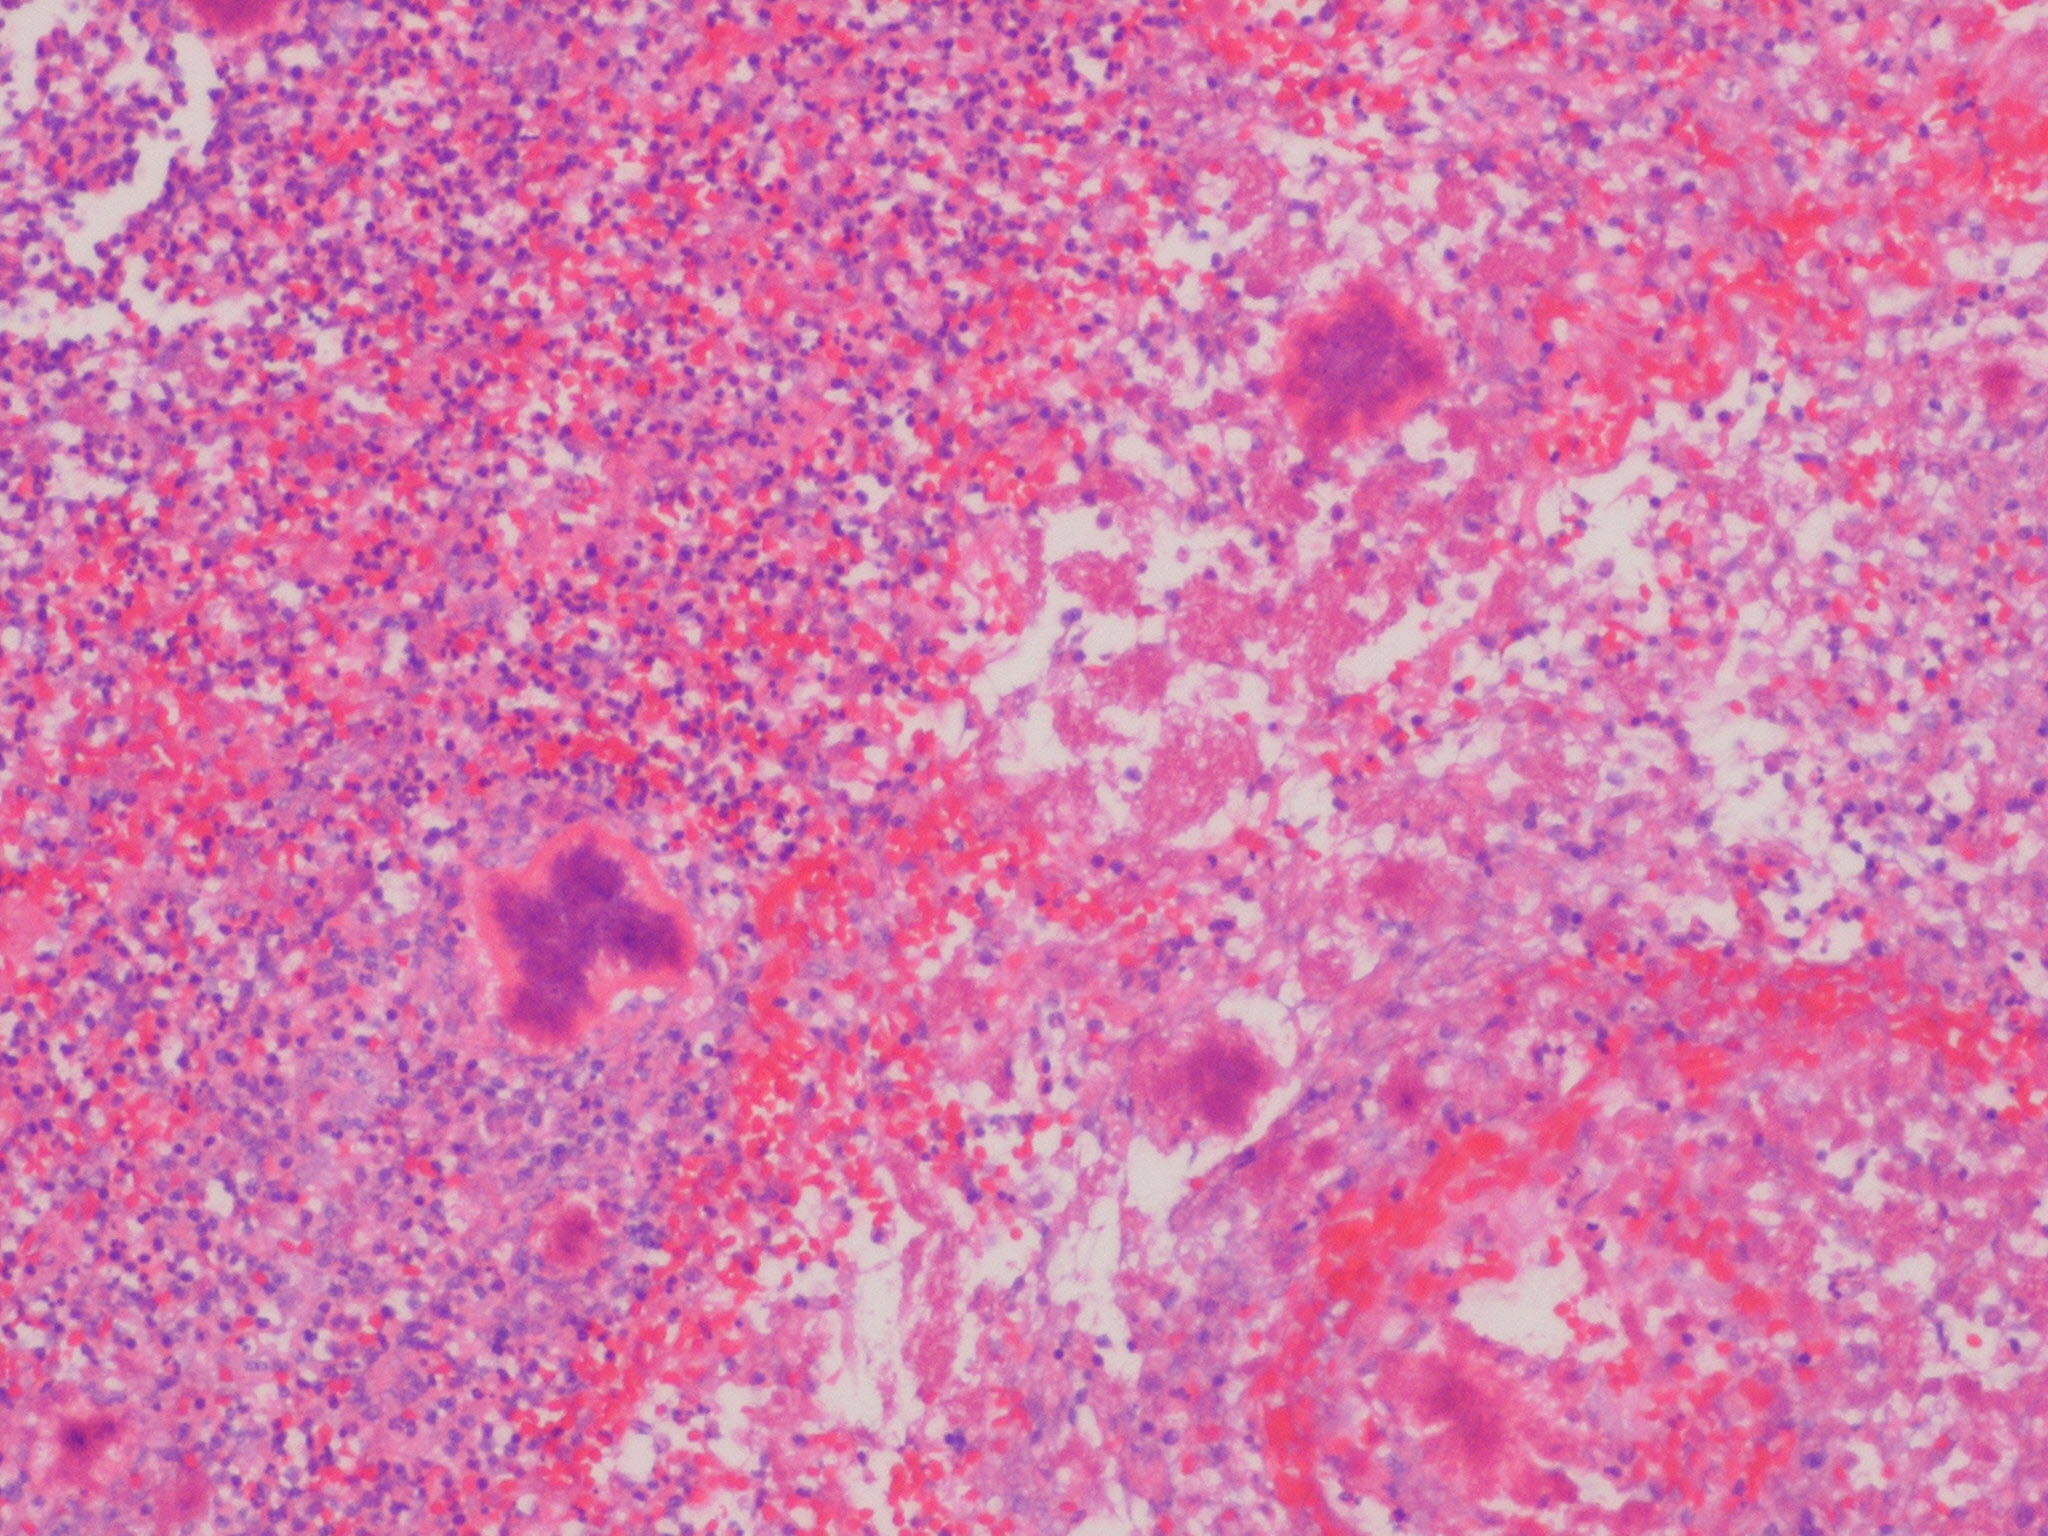

Botryomycosis =الداء العنقودي

OLYMPUS DIGITAL CAMERA